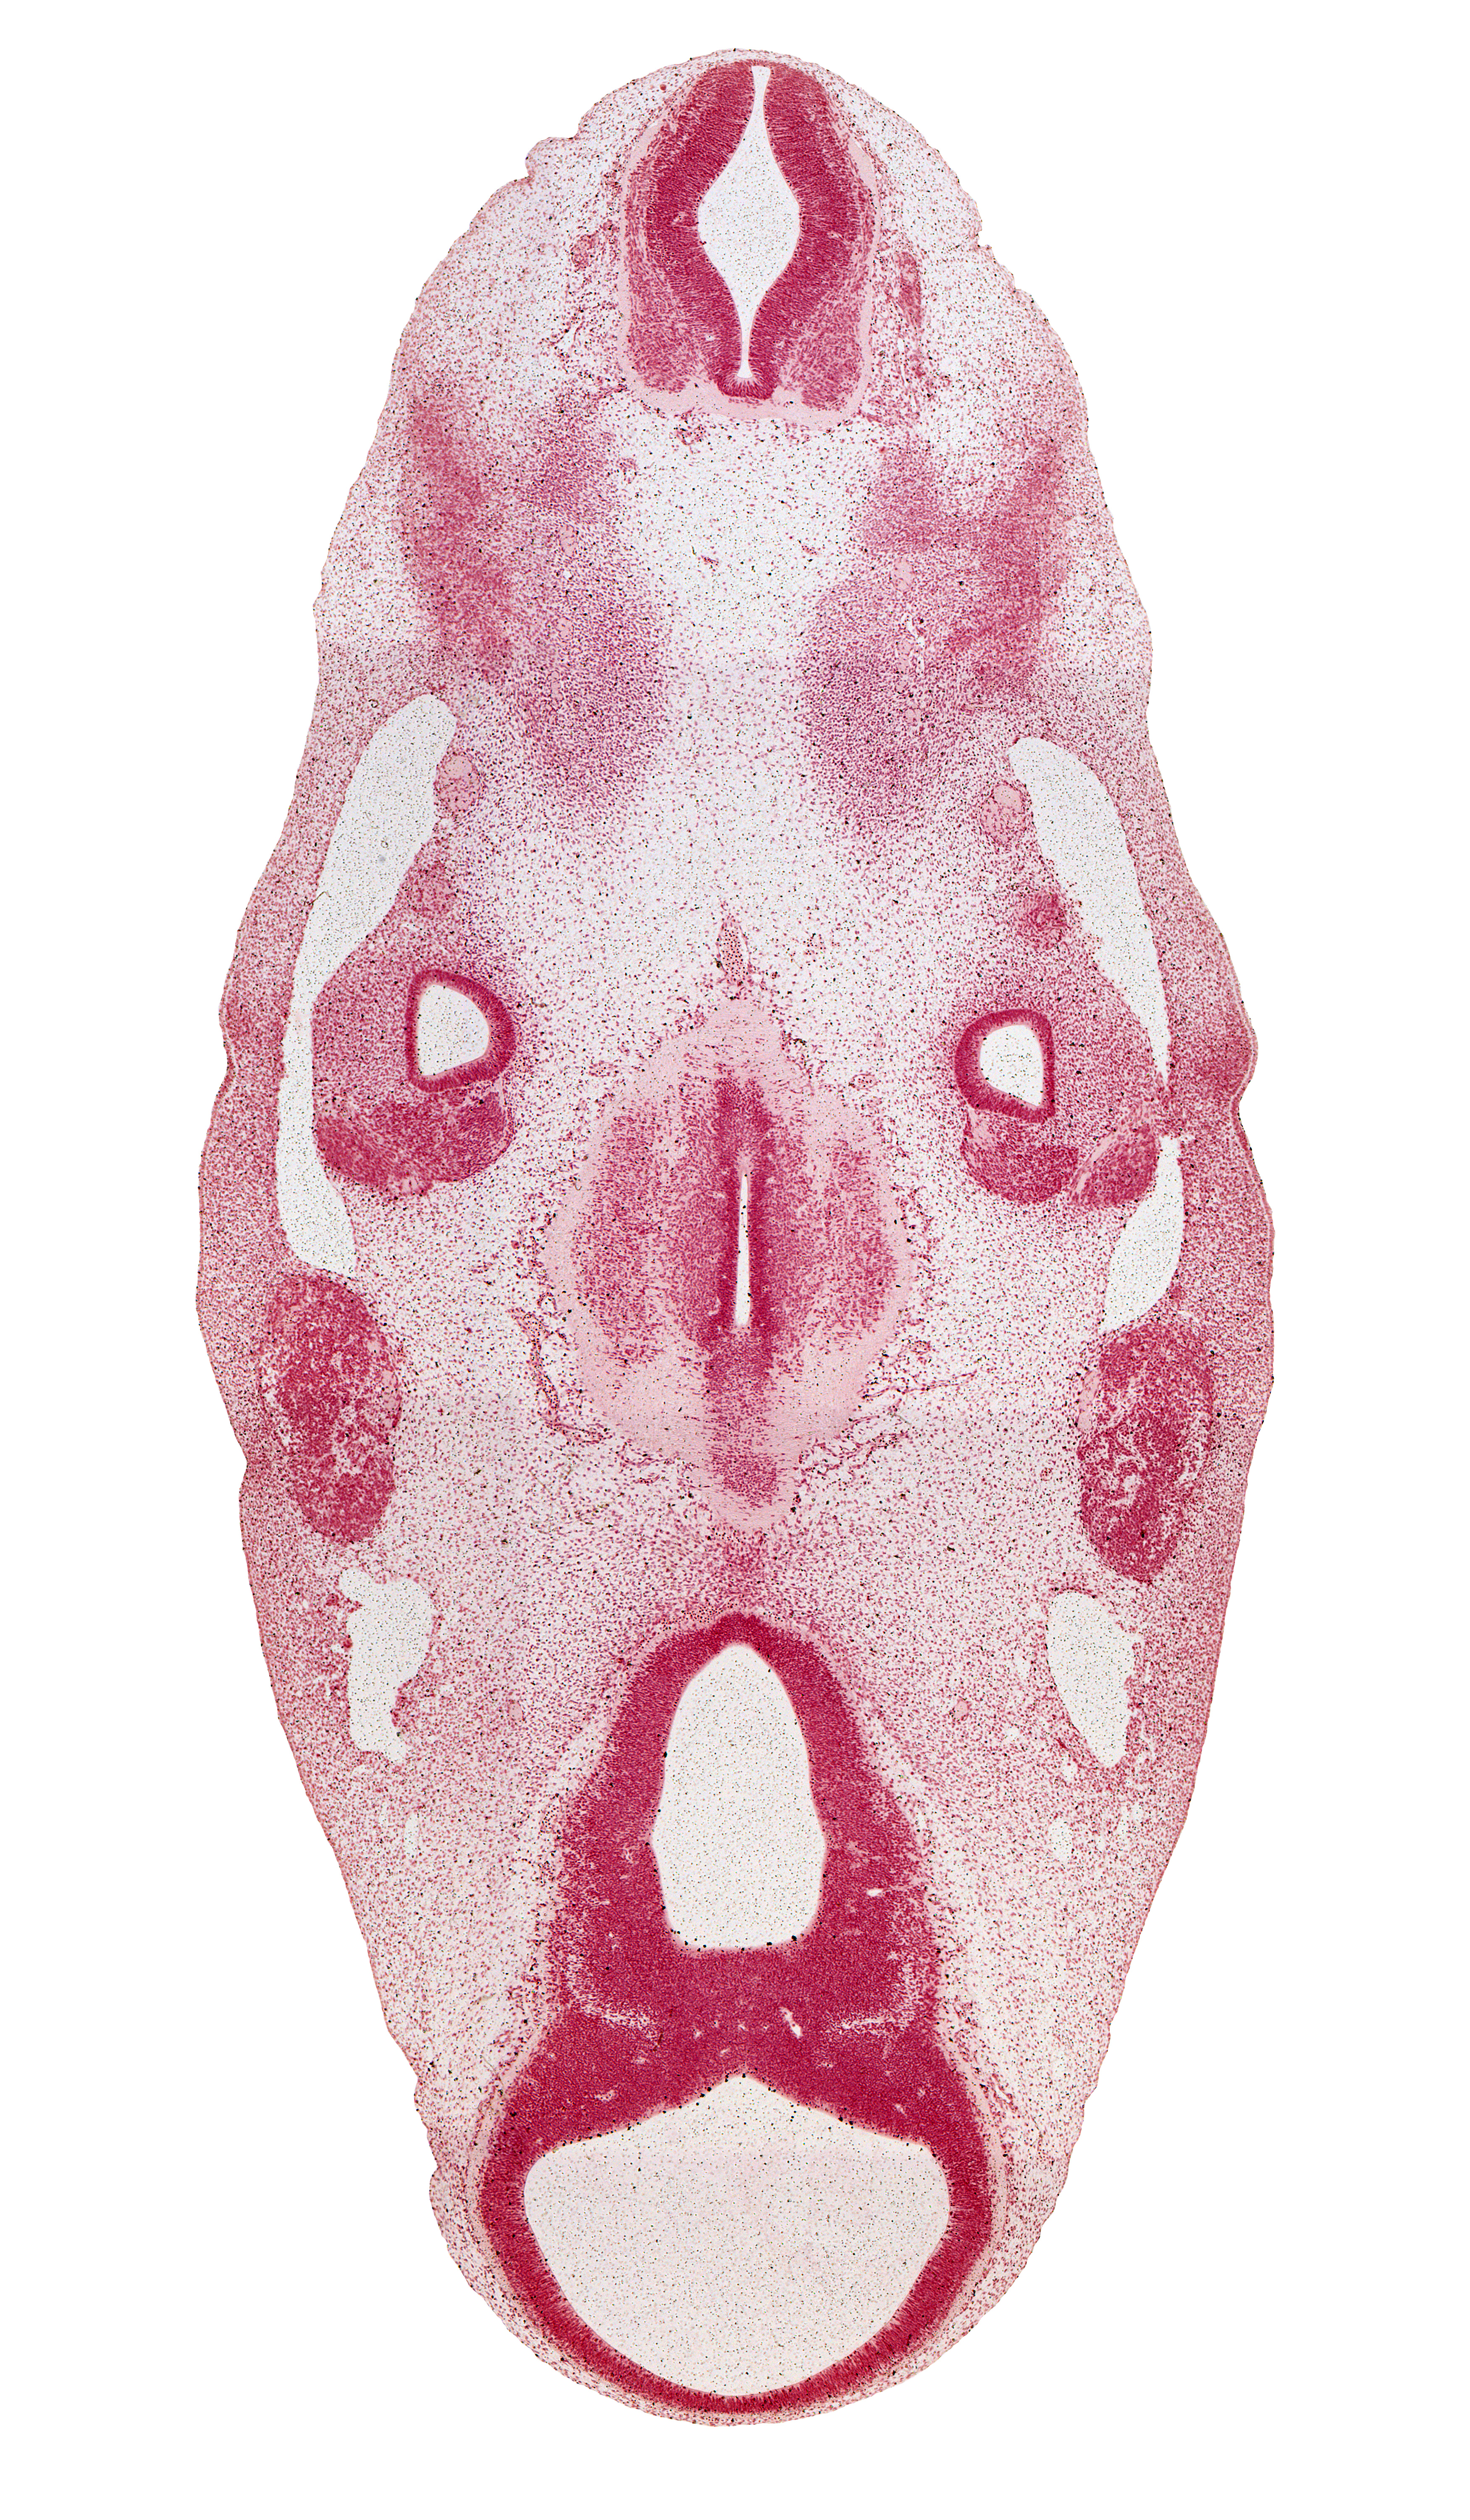

Carnegie Embryo #6517 | Location: 12-01-03

Keywords: C-1 spinal ganglion, accessory nerve (CN XI), basilar artery, caudal edge of rhombencoel (fourth ventricle), central canal, dorsal root(s), geniculate ganglion (CN VII), hypothalamus, inferior ganglion of glossopharyngeal nerve (CN IX), intermediate zone, marginal zone, mesencephalon (M1), mesencoel (cerebral aqueduct), motor root of trigeminal nerve (CN V), neurohypophyseal bud, occipital myotome, oculomotor nerve (CN III), parachordal condensation, subthalamus, sulcus limitans, third ventricle, trigeminal ganglion (CN V), trochlear nerve (CN IV), vagus nerve (CN X), ventral root, ventral thalamus, ventricular zone

Source: The Virtual Human Embryo.